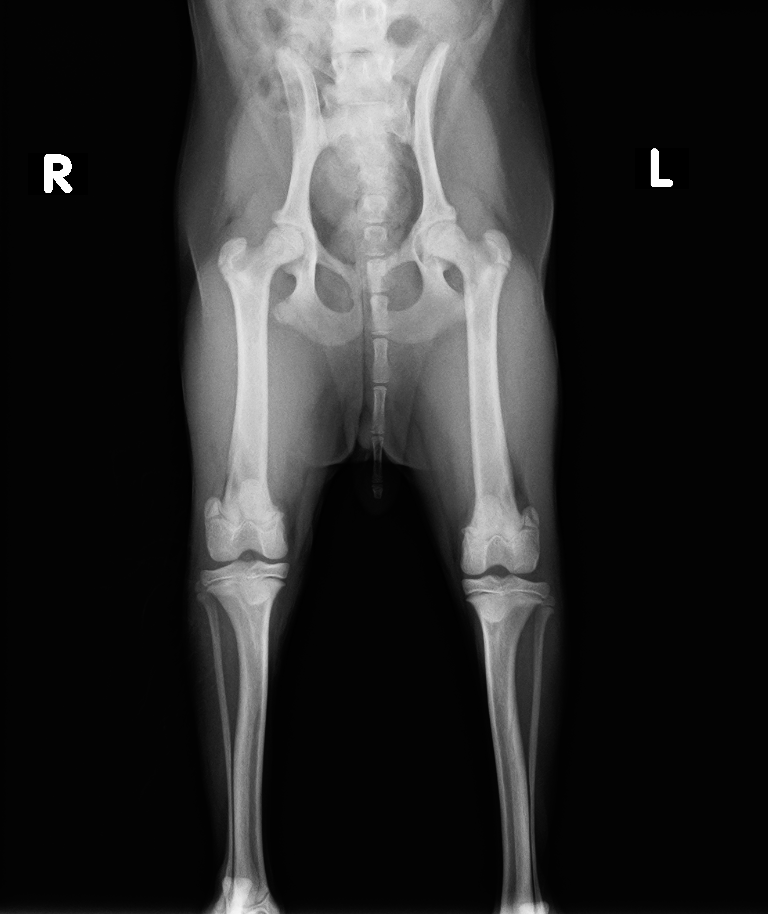

レントゲン検査より、脛骨粗面成長板の剥離

診断と治療

脛骨粗面にKワイヤーを挿入して固定